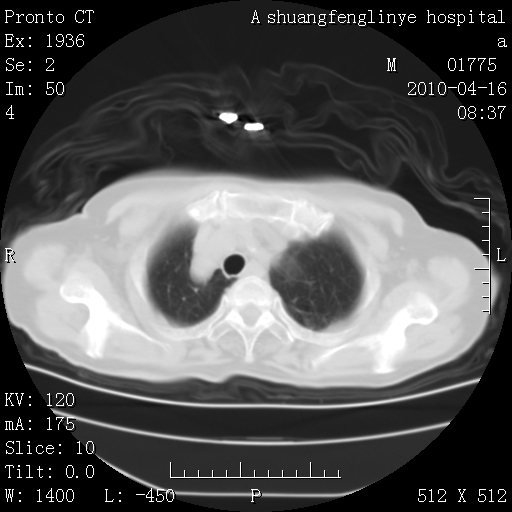

标题: CT25784:咳痰、请会诊!结核? [打印本页]

标题: CT25784:咳痰、请会诊!结核?

陈旧性结核,胃腔扩大,脾脏受压后移

考虑左肺上叶增殖灶、纤维灶。

支持结核

慢支肺气肿,左上陈旧性结核,主动脉冠脉钙化

1)左肺上叶结核(纤维、增殖病灶)。2)冠状动脉及主动脉钙化。